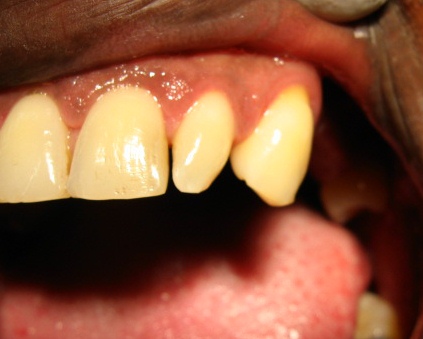

Las anomalías dentales son un grupo de alteraciones morfológicas, que se pueden expresar en la corona o en la raíz dental; aparecen durante el desarrollo de los órganos dentales, se ha establecido que tienen un componente genético y molecular importante. También se han planteado influencias medioambientales, traumáticas y microbiológicas. Las anomalías morfológicas dentarias son comunes, y se presentan con una incidencia de 74,7% según Freer (1998). Los dientes cónicos, en clavija o reducidos tienen una incidencia menor y muestran mayor incidencia en dentición permanente, así como en los incisivos laterales superiores. El mencionado defecto va a ser origen de alteraciones en la oclusión, la longitud de arco, compromisos estéticos que van a afectar la autoestima del paciente. El propósito de este trabajo es presentar dos casos de dientes cónicos, uno en dentición permanente, otro en dentición temporal relacionándolos con el marco teórico encontrado en la literatura sobre las influencias genéticas que juegan un papel importante en la aparición de la mencionada anomalía, aunque no se pudo realizar el estudio genético que se quisiera a causa limitaciones económicas.